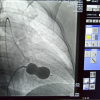

ALKÜ Tıp Fakültesi Öğretim Üyesi Doç. Dr. Cemal Köseoğlu, yaptığı açıklamada, hastanede mitral balon yöntemiyle ilk kez işlem yaptıkları söyledi.

Tıp teknolojisindeki gelişmeler ve giderek artan ameliyatsız müdahale olanaklarıyla artık ciddi kapak müdahalelerini çok düşük risklerle yapabilme olanağı bulduklarını anlatan Köseoğlu, "Hastamız Behice Hanımı, anjiyo ünitemizde hiç uyutmadan mitral balon yardımıyla ile kasıktan girerek daralmış kapağını bir buçuk saat süren işlem sonunda açtık. Son kontrollerimizi yaptık. Hastanın kalp kapağı gayet güzel çalışıyor. 2 gün yoğun bakımda takibi sonunda taburcu işlemlerini gerçekleştireceğiz." ifadelerini kullandı.